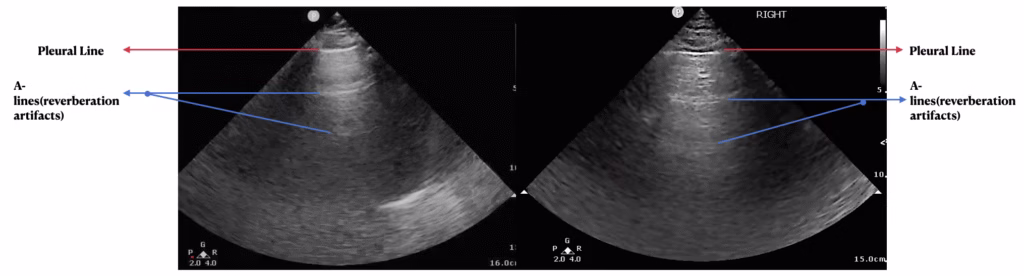

History, physical exam, laboratory, radiological studies, final diagnoses and management decisions were reviewed. We identified three main lung POCUS patterns. These included lung sliding with bilateral A-lines and 0-2 B-lines per lung zone (normal lung POCUS, Figure 1), >2 B-lines bilaterally (predominant B-line pattern, Figure 2) and a predominant A-line pattern with focal, dense B-lines (Figure 3). In addition, patients with unilateral or bilateral pleural effusions (Figure 4) with any of the above patterns were also recorded. Lung POCUS findings were compared with CXRs performed within a 72-hour period, with CT scans, and cardiology-reviewed echocardiograms completed within one month of the lung POCUS examination.

Figure 1. Bilateral predominant A-line pattern seen as a hyper-echoic line at the top of the image representing the pleural line (red arrow) and parallel hyper-echoic lines equidistant from the pleural line called reverberation artifacts (blue arrows).